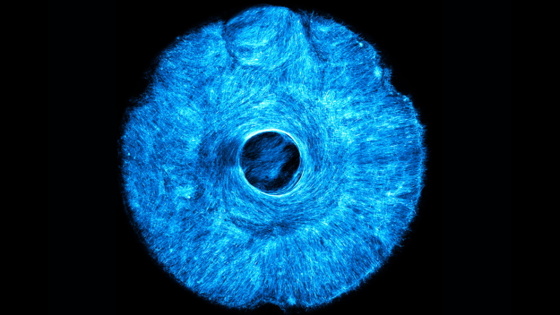

Недавно инженеры Массачусетского технологического института разработали метод выращивания искусственной мышечной ткани, которая двигается и сгибается в нескольких скоординированных направлениях. В качестве демонстрации они вырастили искусственную, работающую на мышцах структуру, которая тянет как концентрически, так и радиально, подобно тому, как действует радужная оболочка человеческого глаза, расширяя и сужая зрачок. Научная статья вышла в Biomaterials Science

Исследователи изготовили искусственную радужку, используя новый подход «штамповки». Сначала на 3D-принтере напечатали небольшой ручной штамп с микроскопическими бороздками, каждая из которых была размером с одну клетку. Затем вдавили штамп в мягкий гидрогель и засеяли полученные бороздки настоящими мышечными клетками. Клетки росли вдоль бороздок внутри гидрогеля, образуя волокна. Когда исследователи стимулировали волокна, мышца сокращалась в нескольких направлениях, следуя ориентации волокон.